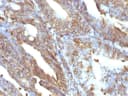

This MAb reacts with a 58 kDa protein identified as vimentin. It shows no cross-reaction with other closely related intermediate filament proteins (IFP's) such as desmin, keratin, neurofilament, and glial fibrillary acid protein. Anti-vimentin alone is of limited value as a diagnostic tool; however, when used in panels with other antibodies, it is useful for the sub-classification of a given tumor. Expression of vimentin, when used in conjunction with anti-keratin, is helpful when distinguishing melanomas from undifferentiated carcinomas and large cell lymphomas. All melanomas and Schwannomas react strongly with anti-vimentin. It labels a variety of mesenchymal cells, including melanocytes, lymphocytes, endothelial cells, and fibroblasts. Non-reactivity of anti-vimentin is often considered more useful than its positive reactivity, since there are a few tumors that do not contain vimentin, e. g. hepatoma and seminoma. Anti-vimentin is also useful as a tissue process control reagent. Primary antibodies are available purified, or with a selection of fluorescent CF® Dyes and other labels. CF® Dyes offer exceptional brightness and photostability. Note: Conjugates of blue fluorescent dyes like CF®405S and CF®405M are not recommended for detecting low abundance targets, because blue dyes have lower fluorescence and can give higher non-specific background than other dye colors.Synonyms:

IHC, FFPE (verified) | WB (verified)Validated Applications:

IHC, FFPE, WBPositive Control:

U-87, Raji, Jurkat or HeLa cells. Sarcomas or Melanomas.Concentration: